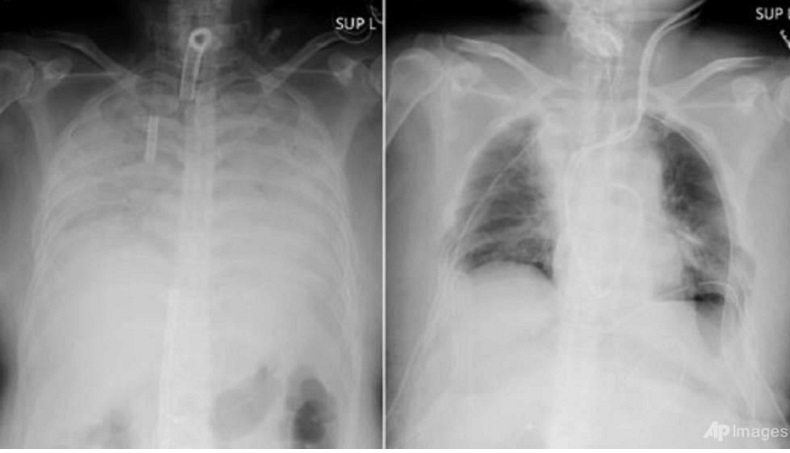

Hasil Rontgen Paru-Paru. (Foto AFP).

TOKYO, iNews.id - Soerang pasien Covid-19 di Jepang menjadi orang pertama di dunia yang mendapatkan transplantasi paru-paru dari pendonor. Perempuan yang paru-parunya mengalami kerusakan itu mendapat donor dari suami dan anaknya.

Rumah Sakit Universitas Kyoto mengatakan, perempuan asal Kansai itu dipastikan dalam kondisi membaik setelah 11 jam menjalani operasi pada Rabu (7/4/2021). Universitas memastikan itu adalah cangkok jaringan paru-paru pertama di dunia dari pendonor ke pasien dengan kerusakan paru-paru yang parah akibat Covid-19.

Sang suami menyumbangkan bagian paru-paru kirinya, dan putranya memberikan bagian paru-paru kanannya. Mereka dilaporkan dalam kondisi stabil setelah menjalani operasi yang ditangani 30 dokter.